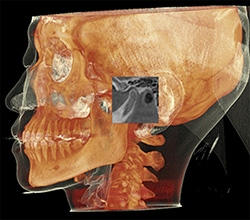

超低被ばく線量のKaVo社製のCBCTを導入しています。このCT装置は、エックス線のパルス照射により、患者様の被ばく線量を最小限に抑えます。